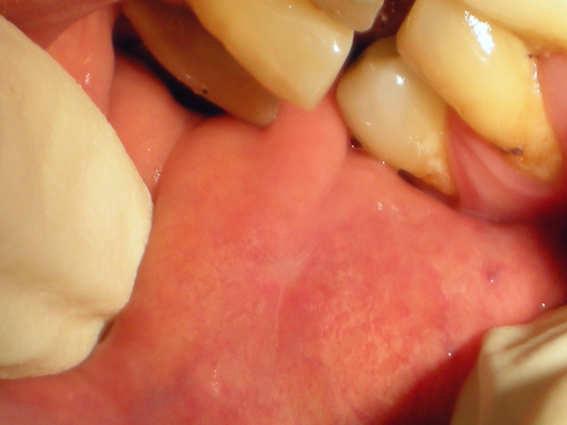

Morsicatio buccarum

Morsicatio buccarum (also known as "Chronic cheek biting," and "Chronic cheek chewing") is a cutaneous condition characterized by chronic irritation or injury to the buccal mucosa from repetitive chewing, biting or nibbling produces characteristic changes in the tissue.